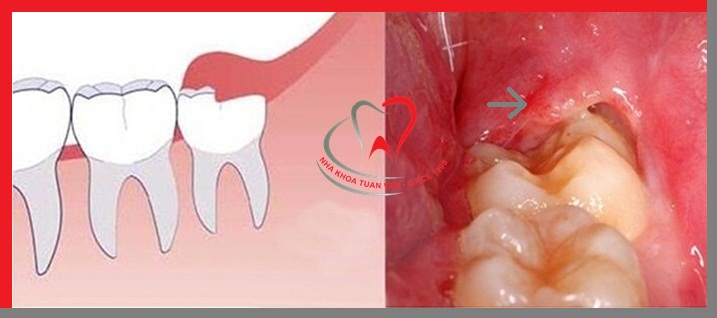

Hình ảnh mô tả hàm răng bị viêm lợi trùm

- Phần lợi bị sưng phồng lên, có màu đỏ, che lấp mặt răng tạo thành một vạt nướu trùm lên răng khôn.